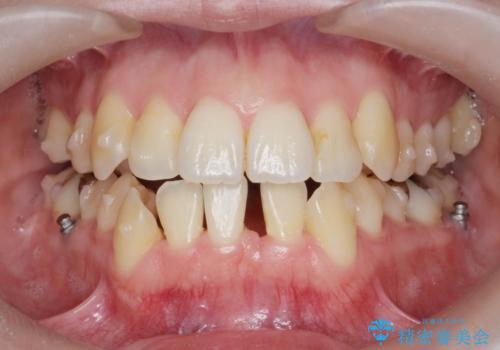

前歯のがたつき すれ違い咬合のマウスピース矯正治療

- 前歯のがたつきや歯の角度、矯正治療を希望され来院されました。

仕事の都合で、ワイヤー矯正を行うことが難しくマウスピース矯正であれば可能、という希望でした。

下顎が前にある咬合関係を可及的に咬合移動で改善し、IPR、下顎3前歯の仕上げで行うマウスピース矯正を計画します。